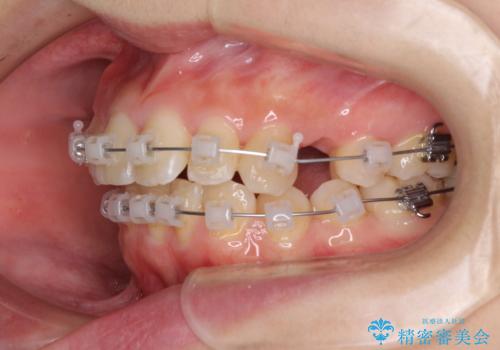

- 矯正装置

- クリアブラケット

- 2年2ヶ月

- 10-30回